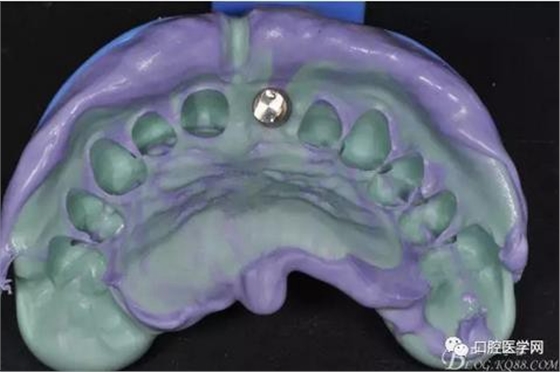

圖11 置閉口印模帽取模

圖12 硅橡膠取模